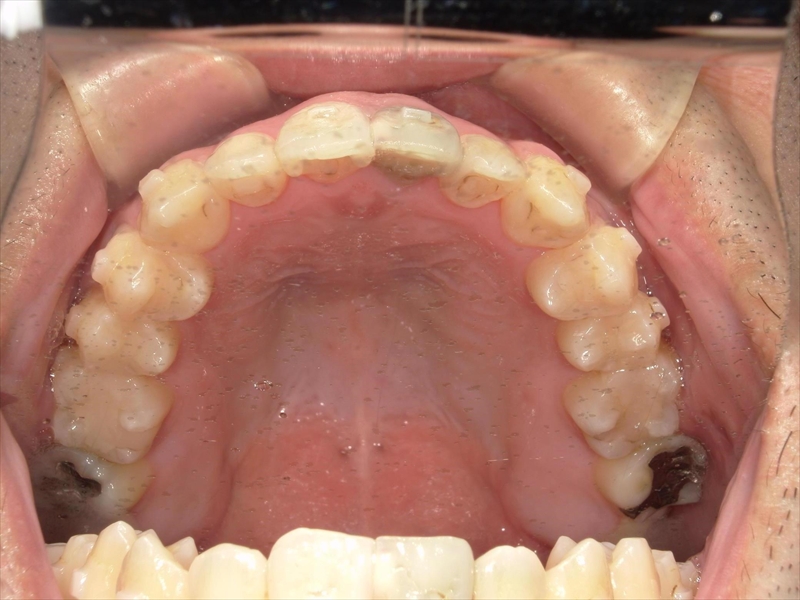

上の歯は歯が並ぶスペースが足りず、八重歯を含むガタガタした歯並びになっていました。

このような状態を改善するため、歯を同じ方向に動かすのではなく、左上の奥歯は後ろへ、右下の奥歯も後ろへと、斜め方向に歯を動かす治療計画を立てました。

これにより、歯並びのズレや噛み合わせの左右差を少しずつ整えていきました。

歯を動かすためのスペースを作る目的で、上の親知らず2本を抜歯し、1本あたりごくわずかに歯を削る処置も行っています。

治療前後 写真